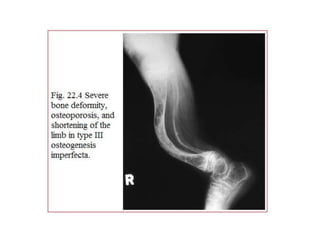

Osteogenesis Imperfecta- Type III

21

This occurs in 15% of the patients, is a severe and

progressively deforming type & is usually due to new

mutation.

Affected individuals suffer from multiple fractures that

start from the initial years of their life result in bowing.

Overall bones are demineralised. Vertebral compression

is seen and a kyphoscoliosis results. The long bones are

osteoporotic and thin.

Sclera may be blue at birth but are usually normal in

adolescence.

In skull ossification is poor, sutures are wide and

wormian bones persists.

It also has association with dentinogenesis imperfecta.